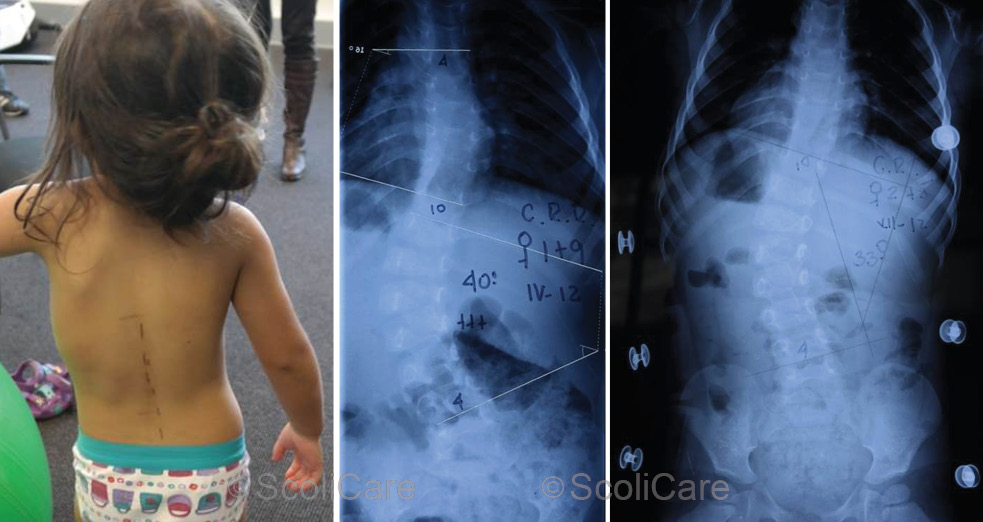

Figure 1: Posteroanterior postural photograph (Left), Initial posteroanterior x-ray (Middle),

In-Brace [Hospital TLSO] posteroanterior x-ray highlighting a 33° thoracolumbar curve (Right).

X-ray imaging ordered by the GP revealed a left thoracolumbar curve measuring 40° and a mild (10°) compensatory right thoracic curve (Figure 1). The GP had made a diagnosis of infantile scoliosis and referred the patient on to an orthopaedic surgeon for an appraisal.

In-brace x-rays taken soon after the TLSO fitting showed a reduction in the size of the primary curve from 40° to 33° (Figure 1). While a reduction in the curve was evident, the parents of the patient had concerns that there was still significant deformity present despite wearing the TLSO. This prompted them to seek a second opinion from the ScoliCare Clinic.